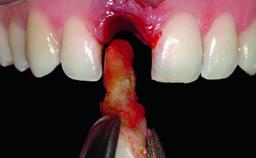

A 36-year-old male patient with a compromised maxillary central incisor was referred by his general dentist for consultation. The patient’s chief complaints were the gradual debonding of a temporary crown on the right central incisor and unsatisfactory esthetics due to an increasing diastema between the right central and lateral incisors. The patient reported a traumatic event some years previously, when a crown had been placed after root-canal treatment. The referring dentist wanted to provide a new crown restoration, but was concerned about the condition of the residual root. Anamnesis was negative for any other dental or periodontal pathology in the remaining dentition. The patient reported taking no medications: He was a smoker (10 to 15 cigs/day) and had realistic esthetic expectations.

Bone Volume Deficient horizontally, requiring prior grafting